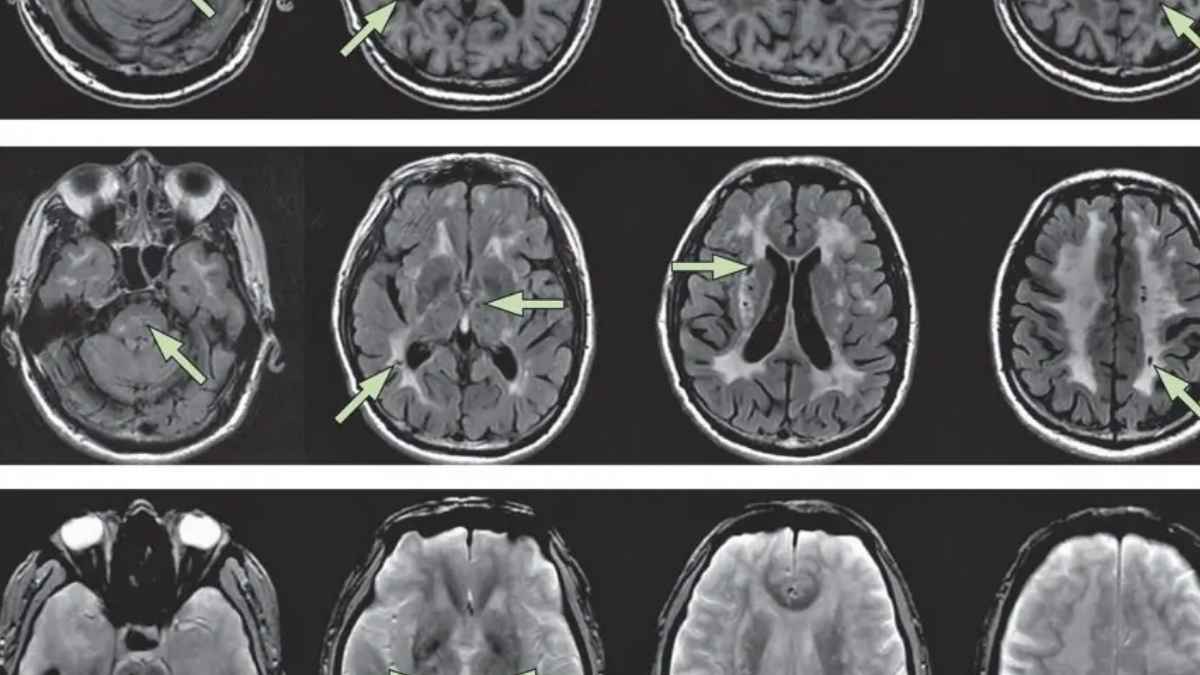

El expediente lo promueve un trabajador autónomo afectado por Cadasil, un trastorno genético raro que daña los vasos sanguíneos del cerebro. ¿El resultado? Reducción del flujo sanguíneo y mayor riesgo de eventos neurológicos serios que impiden trabajar con normalidad.

El Cadasil se asocia a mutaciones en el gen NOTCH3 y a un engrosamiento progresivo de las arterias cerebrales. En este caso, el tribunal valora que las crisis recurrentes y los déficits cognitivos y sensoriales hacen inviable cualquier actividad laboral ordinaria.

La enfermedad suele debutar en la edad adulta con migrañas con aura y puede avanzar hacia accidentes cerebrovasculares repetidos. A partir de ahí, aparecen isquemias que afectan movilidad, memoria y capacidad cognitiva.

También son frecuentes pérdida de fuerza, alteraciones visuales y déficits sensoriales. No obstante, lo determinante aquí es la concurrencia de síntomas y su progresión: el tribunal entiende que las crisis y los déficits del demandante le impiden desempeñar tareas, incluso en empleos menos exigentes.